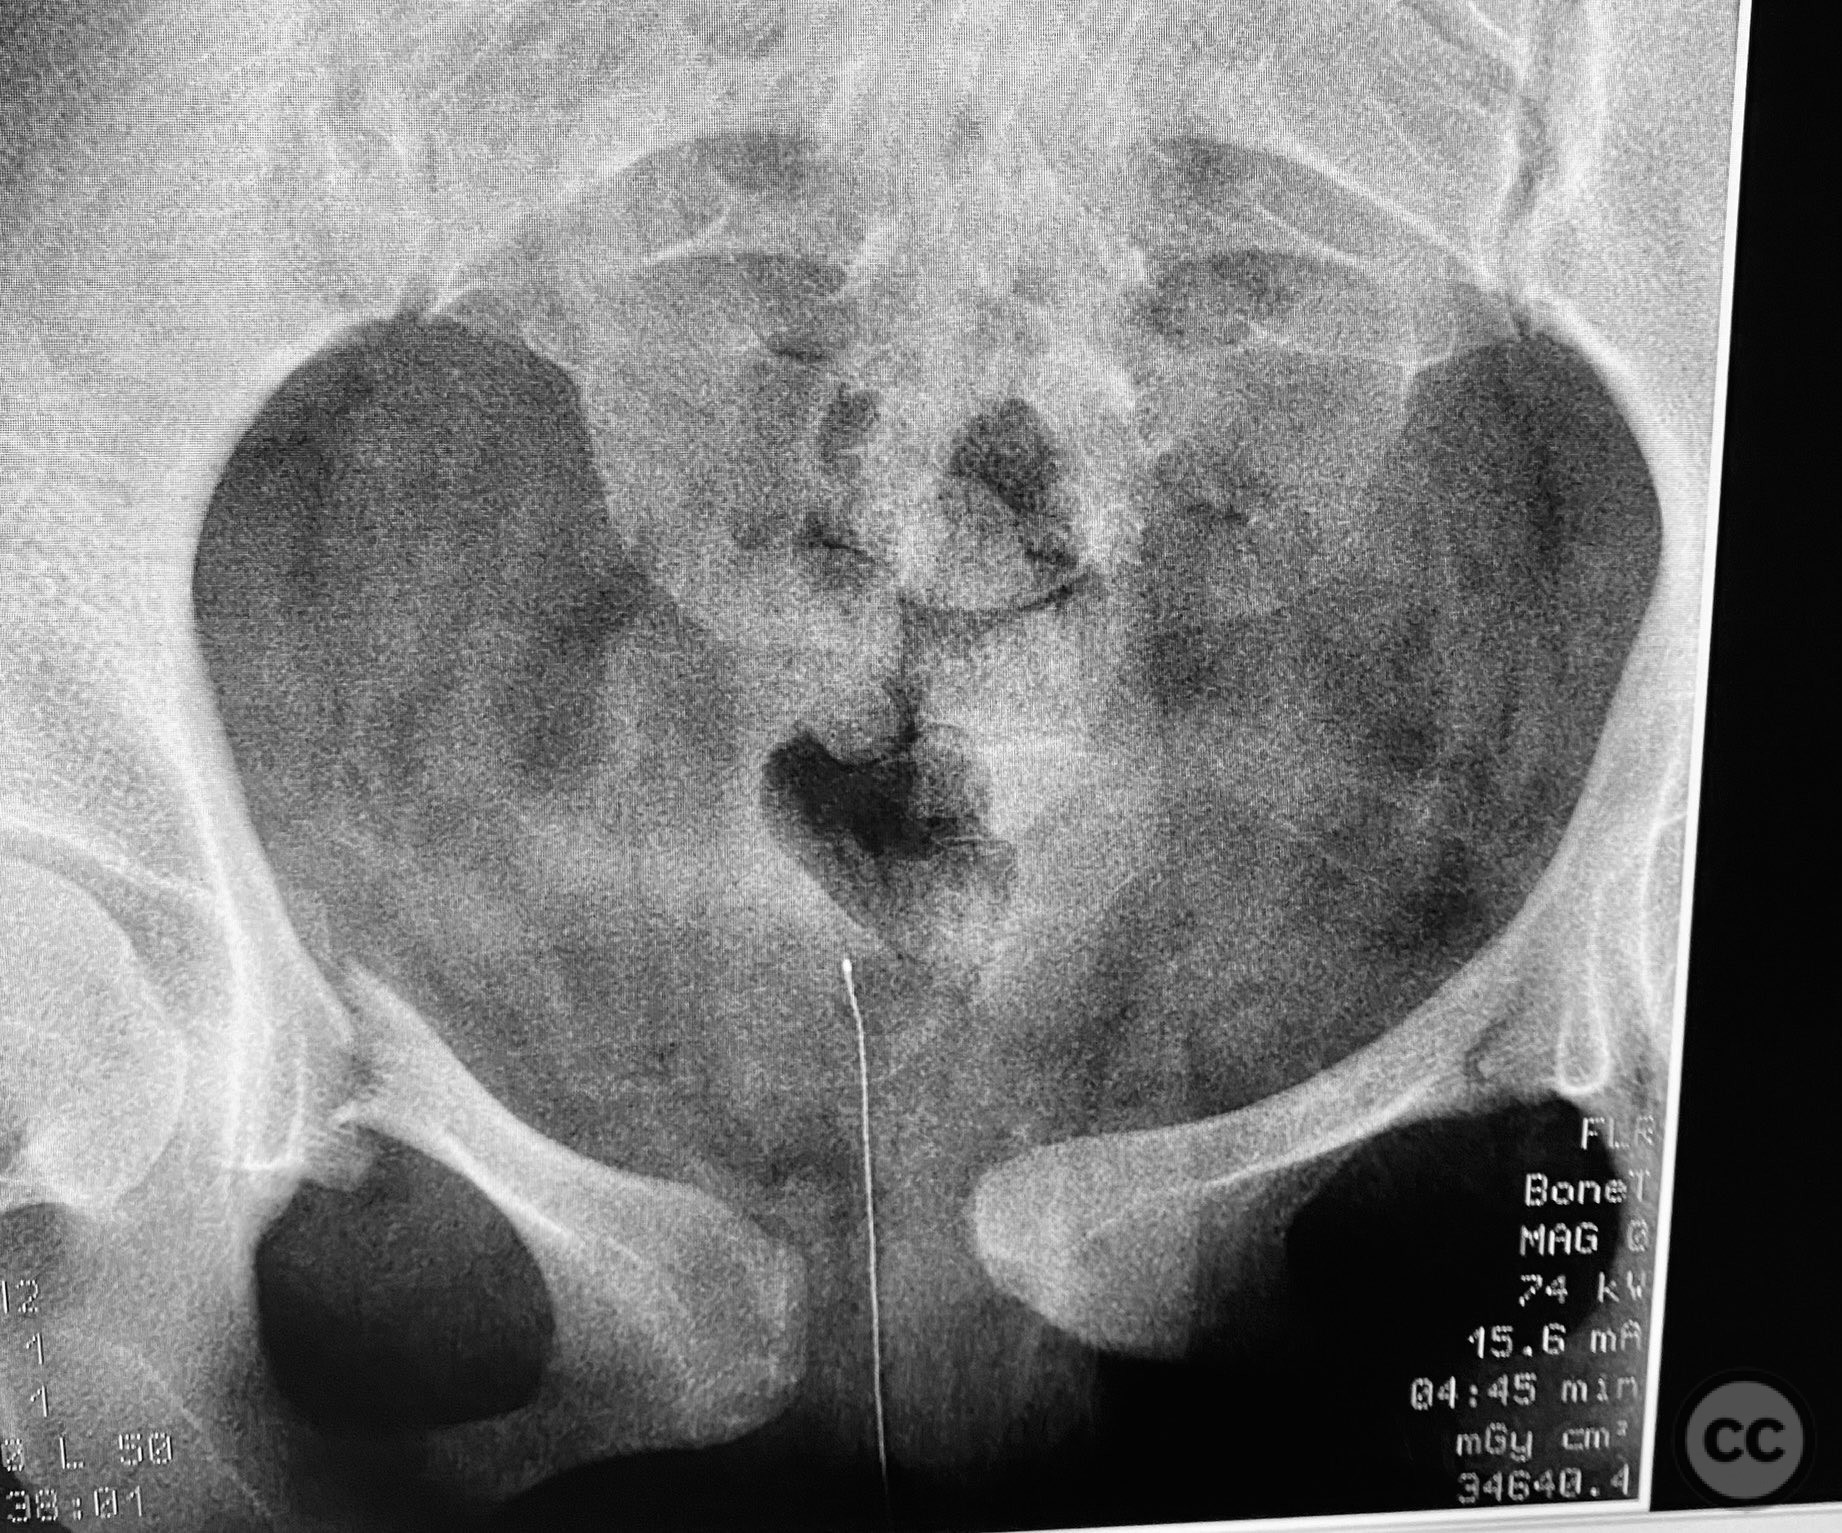

Clinical and radiological findings:  A young adult female sustained a high-energy pelvic injury following a motorcycle crash. She was hemodynamically stable on presentation, with normal neurovascular examination and no evidence of genitourinary, vaginal, or rectal injury. She reported pain localized to both anterior and posterior pelvic regions. Initial plain radiographs (with and without pelvic binder) demonstrated multiple anterior ring fractures and dislocations. The binder images obscured the full extent of injury. Further intraoperative fluoroscopic imaging (AP, inlet, and with lower extremities in "lotus" position) revealed bilateral sacroiliac (SI) joint disruptions (right greater than left), bilateral superior/inferior pubic ramus fractures (right greater than left), and symphyseal diastasis. Notably, the right pubic ramus demonstrated excessive curvature, complicating potential percutaneous screw fixation. AO/OTA classification: 61-C1.3 (bilateral complete disruption of the posterior arch with associated anterior ring injury). Young-Burgess classification: APC III.

Patient positioning:  The patient was positioned supine on a radiolucent operating table under general anesthesia. For intraoperative assessment, the lower extremities were placed in a "lotus" position to enhance visualization of pelvic ring injuries under fluoroscopy.